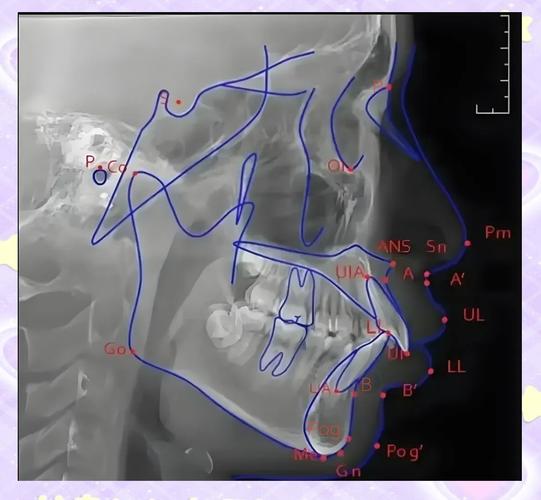

普特正畸头影测量的准确性依赖于对颅颌面解剖标志点的精确定位,以及基于这些点的标准化测量,常用标志点可分为骨骼标志点、牙齿标志点和软组织标志点三大类,测量项目则包括角度、线距、比例等多种类型。

(一)常用标志点定义

| 类别 | 标志点 | 定义/位置 |

|---|---|---|

| 颅底标志点 | Sella (S) | 蝶鞍中心,颅部的参考中心点 |

| Nasion (N) | 鼻额缝的最前点,代表颅部与前部的交界 | |

| 上颌标志点 | A点 (Subspinale) | 上颌骨前壁与牙槽突的最凹点,反映上颌骨相对颅部的位置 |

| Orbitale (Or) | 眶下缘最低点,与构成眶耳平面(FH平面)的关键点 | |

| 下颌标志点 | B点 (Supramentale) | 下颌骨前壁与牙槽突的最凹点,反映下颌骨相对颅部的位置 |

| Pogonion (Pg) | 颏部最前点,代表下颌骨颏部的突度 | |

| Gnathion (Gn) | 下颌骨下缘最下点,垂直参考的重要标志 | |

| 牙齿标志点 | U1 (上颌中切牙) | 上颌中切牙切缘中点或根尖尖点(根据测量需求选择) |

| L1 (下颌中切牙) | 下颌中切牙切缘中点或根尖尖点 | |

| 软组织标志点 | Ns (软组织鼻根) | 软组织鼻额缝的最前点 |

| Pg' (软组织颏前点) | 软组织颏部最前点 |